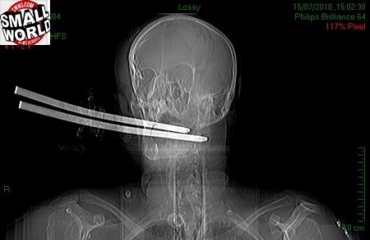

Escocês sobrevive a forquilha cravada no crânio

Hugh Buckley, de 54 anos, sofreu um ataque brutal de um amigo que sofria de paranoia e achava que a sua comida havia sido envenenada. O inglês foi golpeado várias vezes e ficou com uma forquilha (instrumento agrícola com cabo de madeira e com dois dentes de metal em uma das pontas, usado para remover folhas, palha e feno) cravada no crânio.

A vítima só foi achada um dia depoisOs bombeiros retiraram o cabo da forquilha e levaram Hugh para um hospital de Glasgow (Escócia). O agressor, Thomas Pollock, fugiu da cena do crime - a sua própria casa.